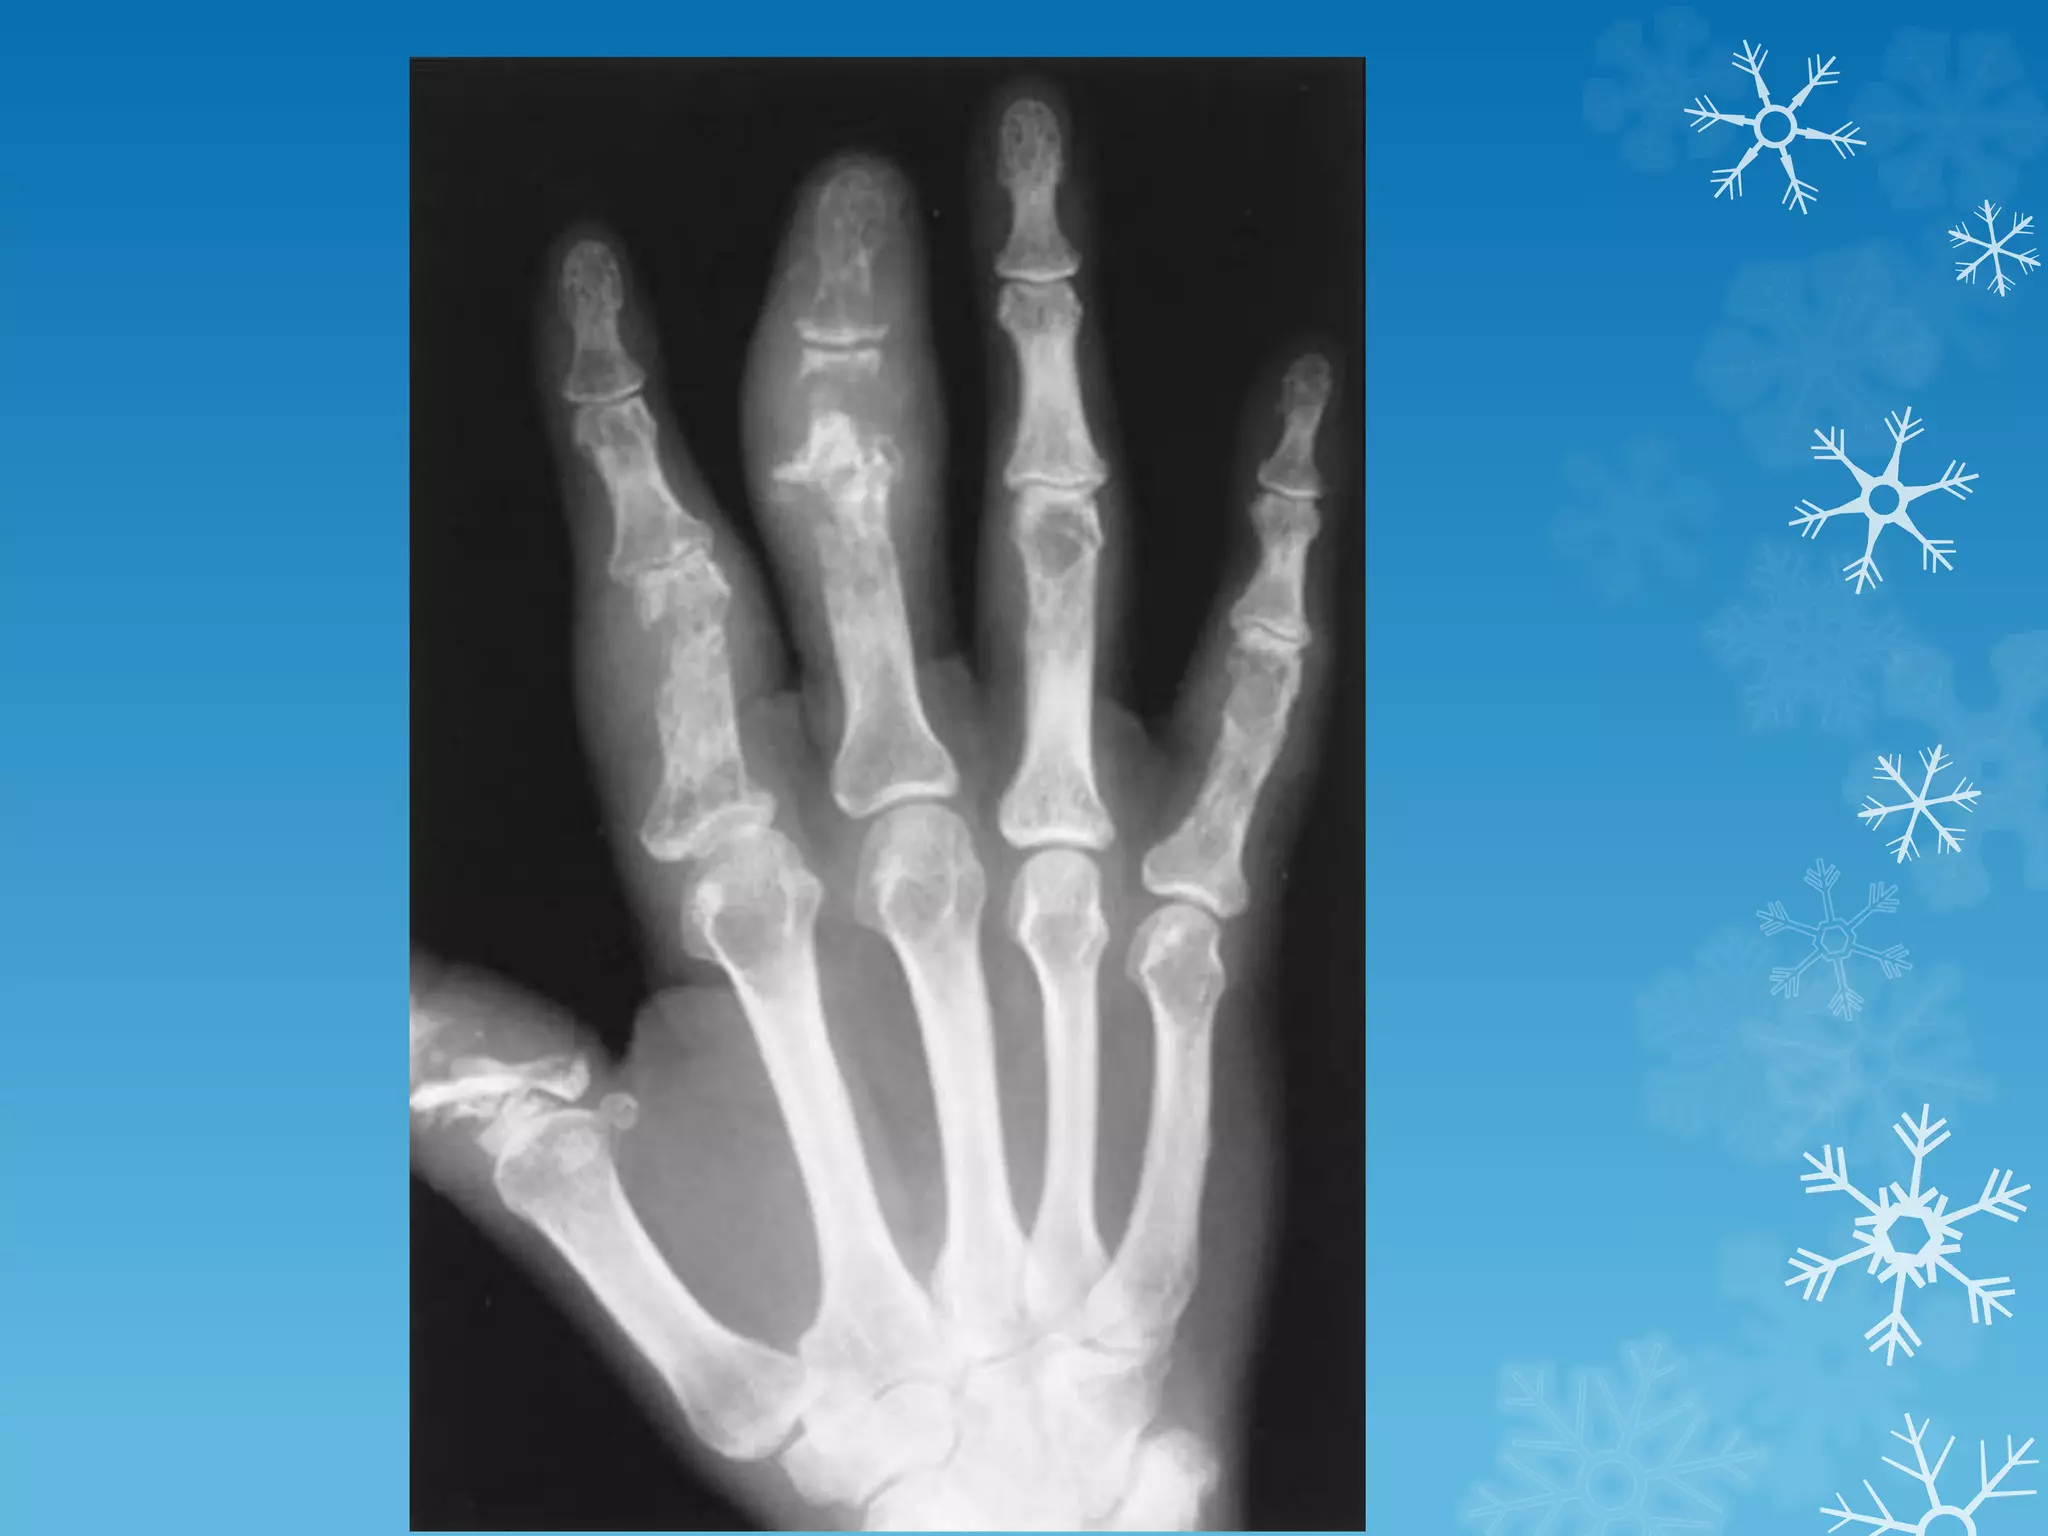

Anteroposterior view of the hand in this patient with sarcoid

demonstrates classic changes of bony involvement with this

granulomatous process.

Note the lacelike pattern of destruction, which is seen most

prominently in the proximal phalanges and in the distal third

phalanx.

Soft tissue swelling and some areas of severe bony dissolution

are also noted, which occur in more advanced patterns of

sarcoid.

These changes are typically limited to the hands but can rarely

occur in other parts of the skeleton.